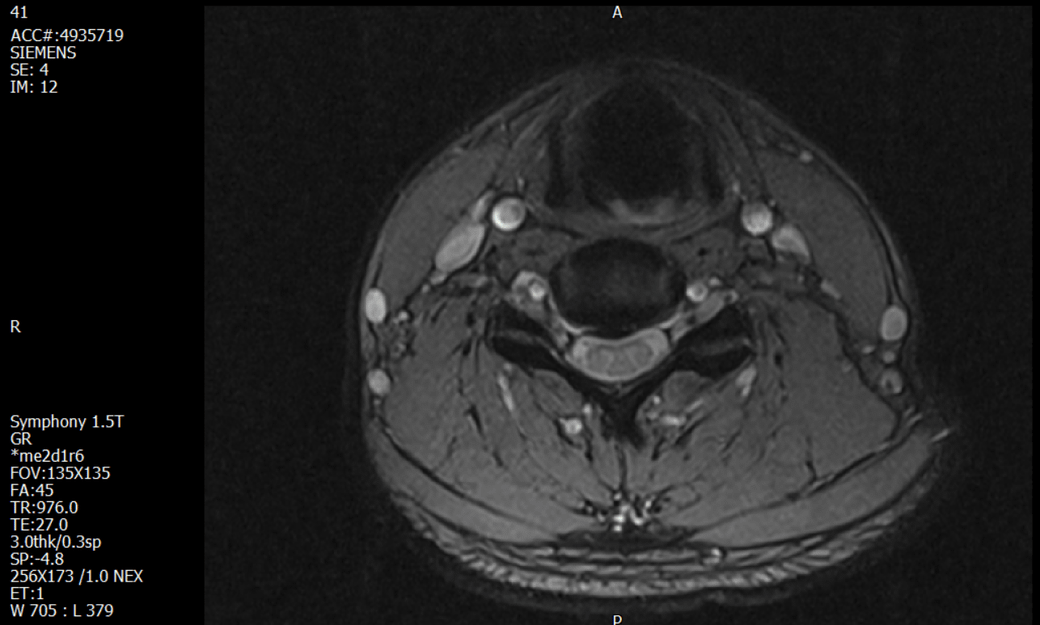

경추 요추 디스크 MRI판독 부탁드립니다.

- 3개월전 좌측 상지 저림(힘빠짐) 발생. 이틀뒤 에 좌측 하지 저림(힘빠짐) 발생.

-11월, 증상발생 직후 잠실소재 척추전문병원 MRI 요추경추 촬영 후 신경외과 박사 진료, 허리는 매우 건강, 경추는 퇴행성 진행되고 있지만 디스크라고 보기 어려움. 신경막만 살짝 건드리는 정도고 이 정도로 힘빠짐이나 저림이 오지 않고 원인은 다른 곳에 있을 가능성.

1. MRI 상 , 경추와 요추에 디스크가 있나요? 있다면 좌측 팔과 다리에 저림 및 힘빠짐을 줄 정도인가요?

• 3번 째 사진

• 1. MRI 사진을 보았을 때 디스크를 의심해볼 수 있는 소견이 살짝살짝 보이긴 합니다만, 상하지의 저림 및 힘빠짐을 유발할 정도인지는 솔직히 회의적입니다.

2. 영상의 퀄리티는 나쁘지 않아 보입니다. 굳이 재촬영을 하실 필요는 없어 보입니다.

3. 개인적으로는 디스크로 인한 증상이 아닐 것으로 보나, 만약 디스크가 맞다면 우연하게 목과 허리 디스크 발병이 이틀 간격을 두고 나타났을 가능성을 생각해야 하는데, 현실적으로 그 가능성이 높지 않습니다.

4. 말씀하신 것처럼 특히 요추부 MRI는 디스크를 찾기 어렵습니다.

상기 MRI 소견으로는 심한 증상을 보일 정도는 아니며 디스크의 가능성은 적어보입니다.